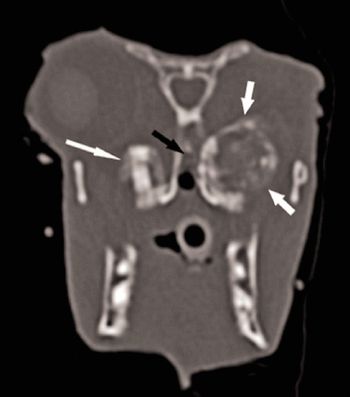

After an enucleation, purulent material began coming from this rabbit's nose and filled the empty orbit. Find out why.